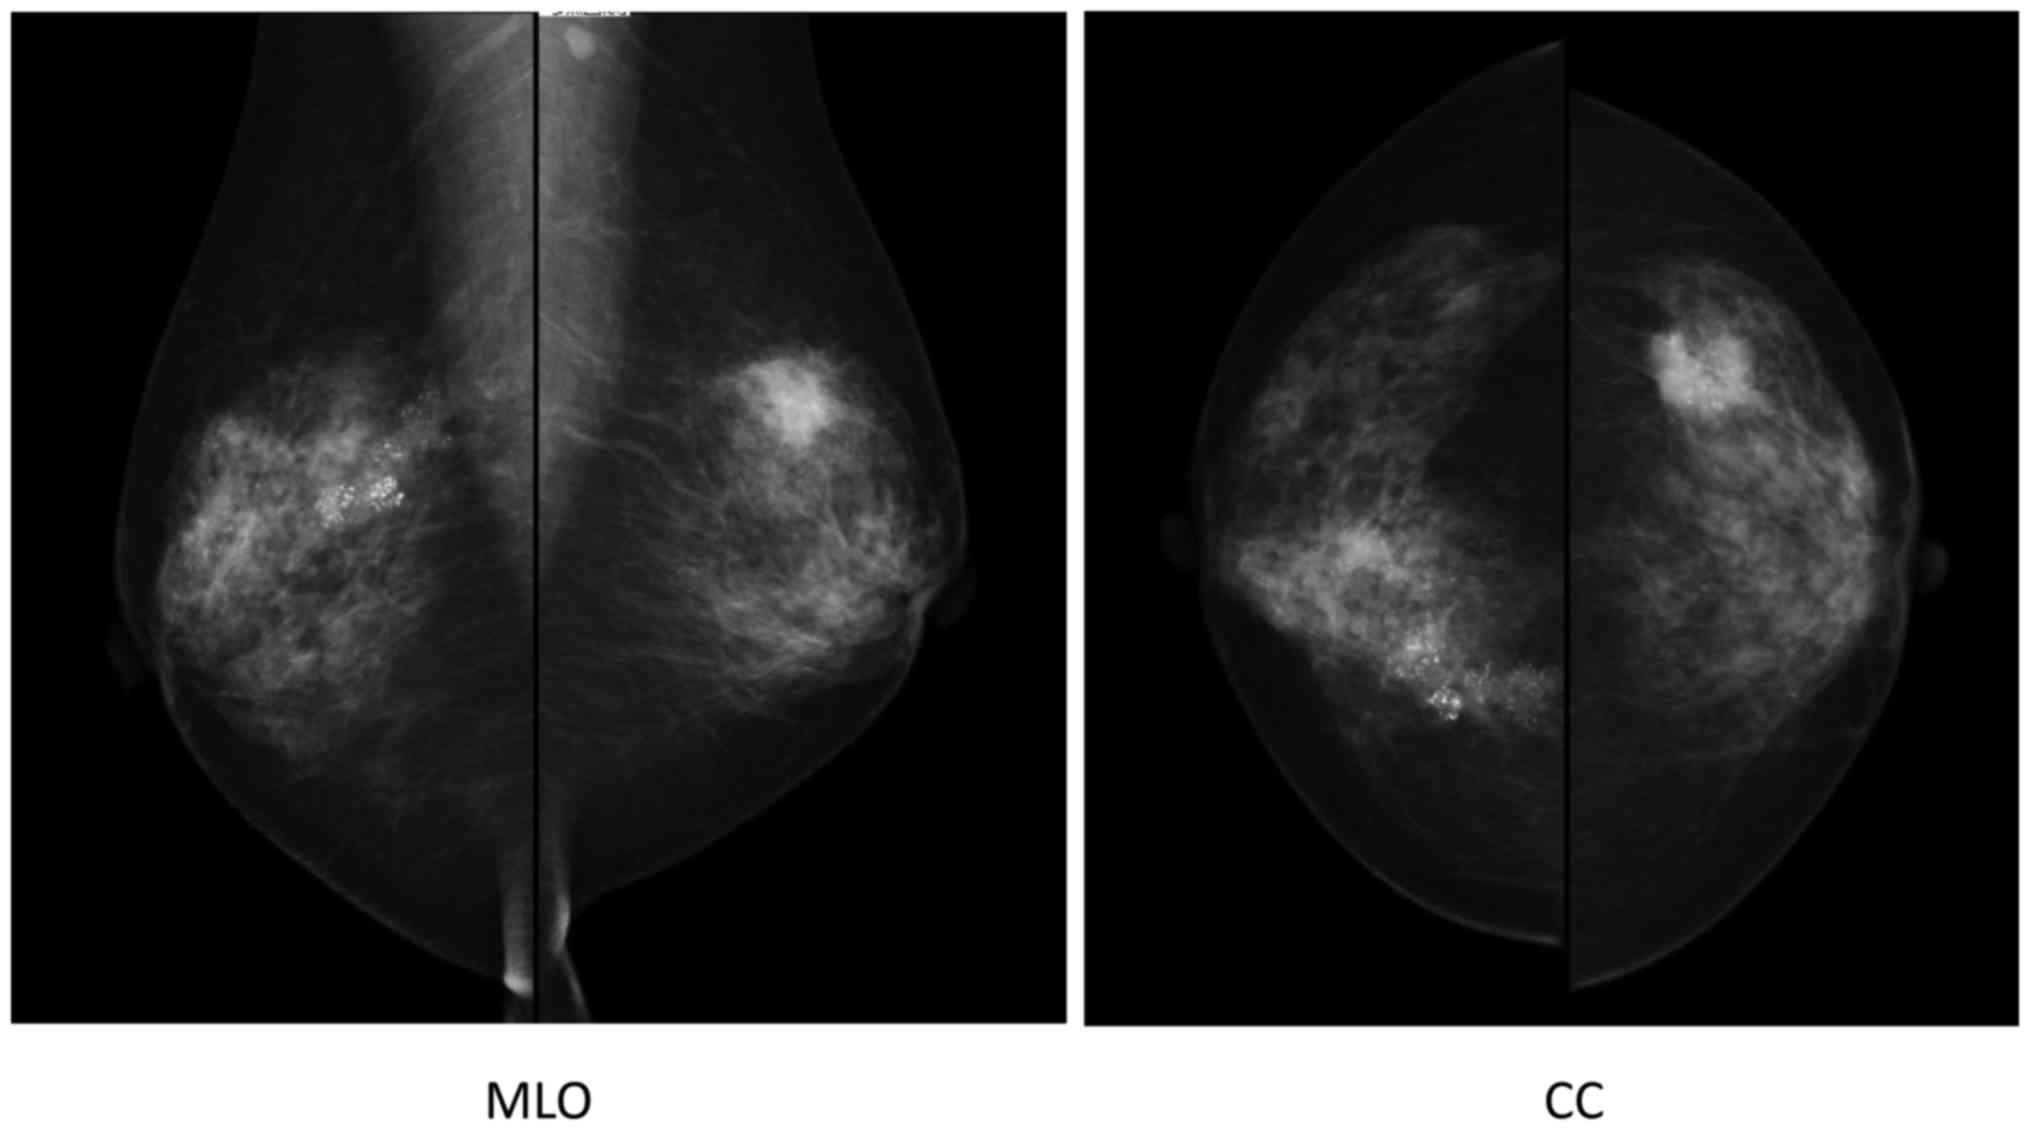

The cytology of nipple discharge was performed by the clinic, revealing the presence of malignant cells. Mammography indicated segmental pleomorphic calcification in the right breast, and a spiculated polygonal tumor measuring 2 cm in diameter with pleomorphic calcification in the left breast. Furthermore, an irregularly shaped axillar lymph node was observed on the left side (Fig. 2).

Figure 2.

Mammography, showing segmental pleomorphic calcification in the right breast and a spiculated polygonal tumor measuring 2 cm in diameter with pleomorphic calcification in the left breast. Furthermore, an irregularly shaped axillar lymph node was observed on the left side. MLO, mediolateral-oblique (view); CC, cranial-cadual (view).